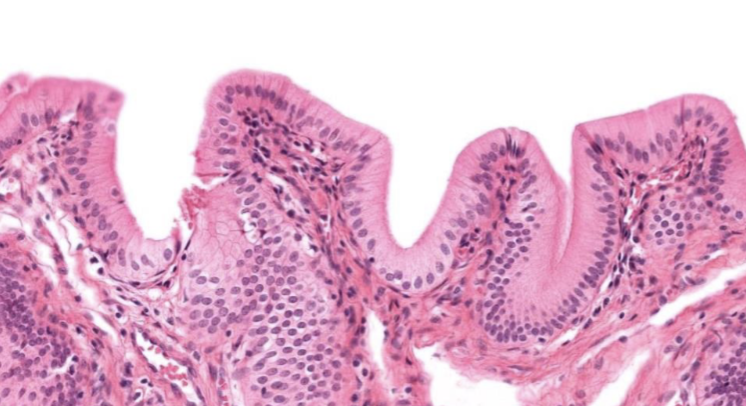

Clasifique tejido epitelial

urotelio

Indique sitio anatómico donde se encuentra

vejiga